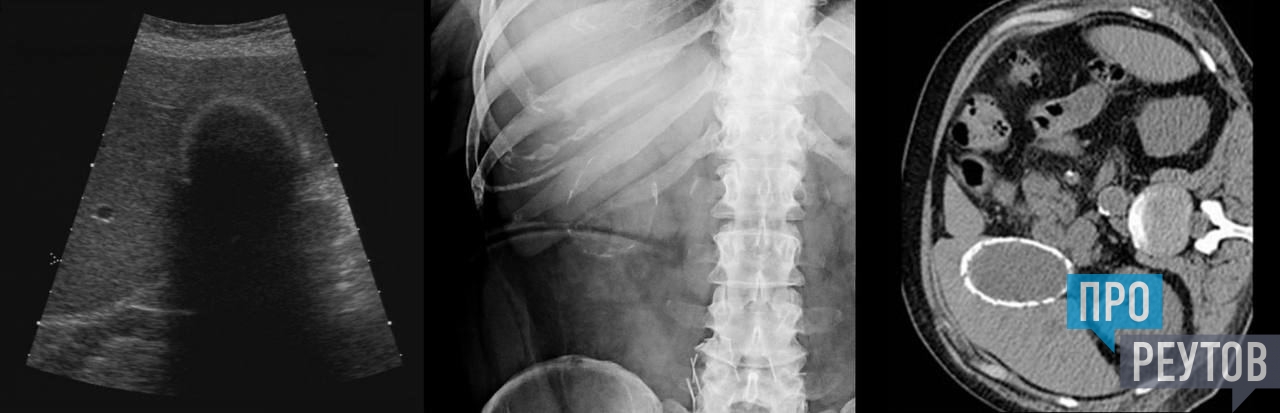

Сейчас с женщиной всё хорошо, она уже выписана. На фото с исследований видно, как необычно выглядит фарфоровый пузырь.